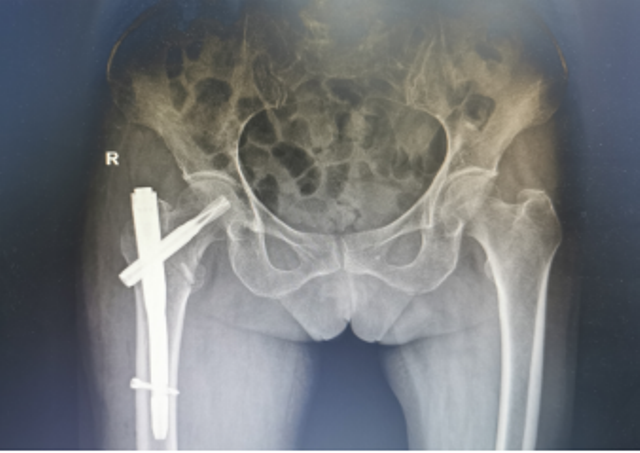

近日,陕西省第四人民医院骨科再次成功为一例91岁高龄的右股骨粗隆间骨折合并冠心病脑梗塞、贫血者实施右股骨粗隆间骨折闭合复位股骨近端抗旋转髓内钉内固定术(简称:PFNA内固定术)。经过术后精心的治疗与护理,患者现已转到康复医学科继续康复治疗。

为了手术能顺利开展,骨一科何大鹏主任通过医务科邀请心血管内科、麻醉科、呼吸与危重症医学科、重症医学科等启动围手术期管理专家团队进行会诊,拟定“右股骨粗隆间骨折闭合复位PFNA内固定术”的手术方案,并制定了一套缜密的术前、术中、术后诊疗康复方案,完善术前准备。3月26日,在麻醉科、手术室团队的密切配合下,何大鹏主任、刘玉春、赵鑫医师为万奶奶成功实施手术,整个术程一气呵成,既缩短手术时间,也减少术中出血,有效降低手术给患者带来的伤害。